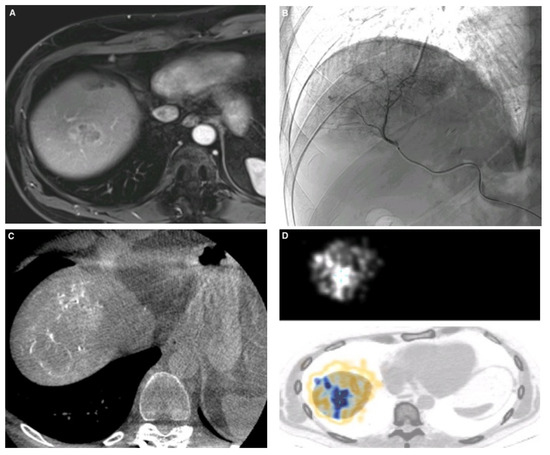

2.4. Workup Procedure

2.5. Treatment Phase